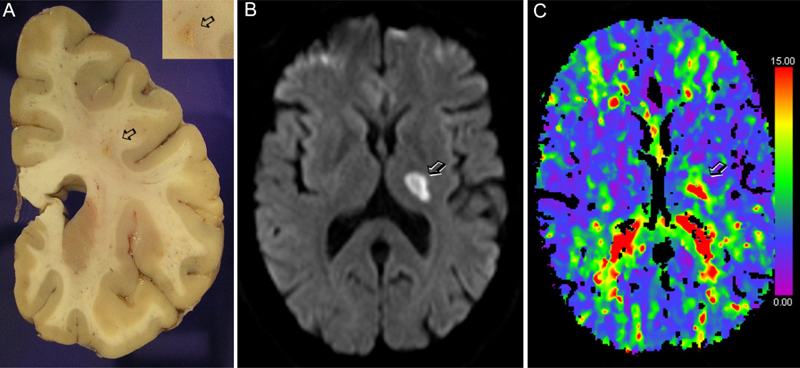

In addition to studies examining monogenic forms of small vessel disease, there are efforts to study genetic variation in large cohorts of patients to identify genes involved in sporadic small vessel disease. Genome-wide association studies correlating variants with MRI features of sporadic small vessel disease may lead to the identification of new putative pharmacologic targets. Small vessel disease is often diagnosed on MRI, with characteristic findings including white matter hyperintensities and signs of lacunar infarcts (Fig. 2). Some recent studies investigated the relationship between genetics and white matter hyperintensities in small vessel disease. Traylor et al (2019) carried out a genome-wide association meta-analysis of white matter hyperintensity volumes in 11,226 subjects, including 2,797 stroke patients. The study identified a locus at genome-wide significance in an intron of Pleckstrin Homology and RhoGEF Domain-Containing Family G Member 1 gene (PLEKHG1) associated with white matter hyperintensities. The association was validated in an independent cohort where this polymorphism was related with ischemic strokes. The strongest association was found with small vessel stroke. PLEKHG1 plays a role in vascular endothelial cell reorientation in response to mechanical stress. Therefore, the polymorphism in this gene could generate some form of vascular alteration leading to the development of white matter hyperintensities. This study also validated 2 previously identified genes EFEMP1 and TRIM47/TRIM65. According to current knowledge, EFEMP1 encodes the Fibulin3 protein, which is an extracellular matrix glycoprotein that inhibits TIMP3. TIMP3 contributes to cerebrovascular dysfunction in CADASIL through accumulation in the vascular extracellular matrix. Therefore, there seems to be some concordance between genetic alterations in sporadic small vessel disease and the monogenic form of CADASIL. Based on the concept that polymorphisms in genes involved in monogenic forms of small vessel disease may have some contribution in the sporadic form of the disease, Mishra et al. (2019) carried out the first whole exome sequencing study on MRI white matter hyperintensities in small vessel disease. This work used a composite extreme phenotype study focused on candidate genes with mutations causing Mendelian heritable forms of small vessel disease, i.e. NOTCH3, HTRA1, COL4A1, COL4A2 and TREX1. The study identified significant associations of gene variants in HTRA1 and NOTCH3 with the development of white matter hyperintensities. Overall the study demonstrates shared mechanisms between monogenic forms and multifactorial forms of small vessel disease. The study suggested that the risk HTRA1 allele reduced HTRA1 expression. Mutations in HTRA1 are associated with cerebral autosomal recessive arteriopathy with subcortical infarcts and leukoencephalopathy, CARASIL, a condition inherited in an autosomal recessive pattern. HTRA1 is a serine-protease involved in cleaving extracellular matrix proteins, including Fibulin3, and regulating important signaling pathways such as the insulin growth factor and TGFß pathway, which suffers an inhibitory effect. Notably, HTRA1 is differentially expressed in astrocytes (Chen et al., 2018) suggesting that dysfunction of this pathway may alter astrocyte function leading to compromised integrity of the neurovascular unit and the BBB. Hopefully additional studies using iPSC from patients and genetically modified animal models further investigating molecular targets identified in prior genetic studies will lead to the discovery of treatments to prevent and attenuate the progression of small vessel disease.

Figure 2. Lacunar infarcts typical of small vessel disease. A) Human brain tissue showing a lacunar infarct (arrow) in the centrum semiovale. Image obtained by Dr. Iban Aldecoa, Neurological Tissue Bank of the Biobank of Hospital Clínic - IDIBAPS - University of Barcelona. B) MRI showing a thalamic lacunar infarct (arrow) and C) corresponding CT-perfusion time-to-drain (TTD) image obtained in the acute phase showing a delay in blood flow in the lacunar infarction (arrow). Images in B and C were obtained in the Comprehensive Stroke Center of Hospital Clinic of Barcelona.